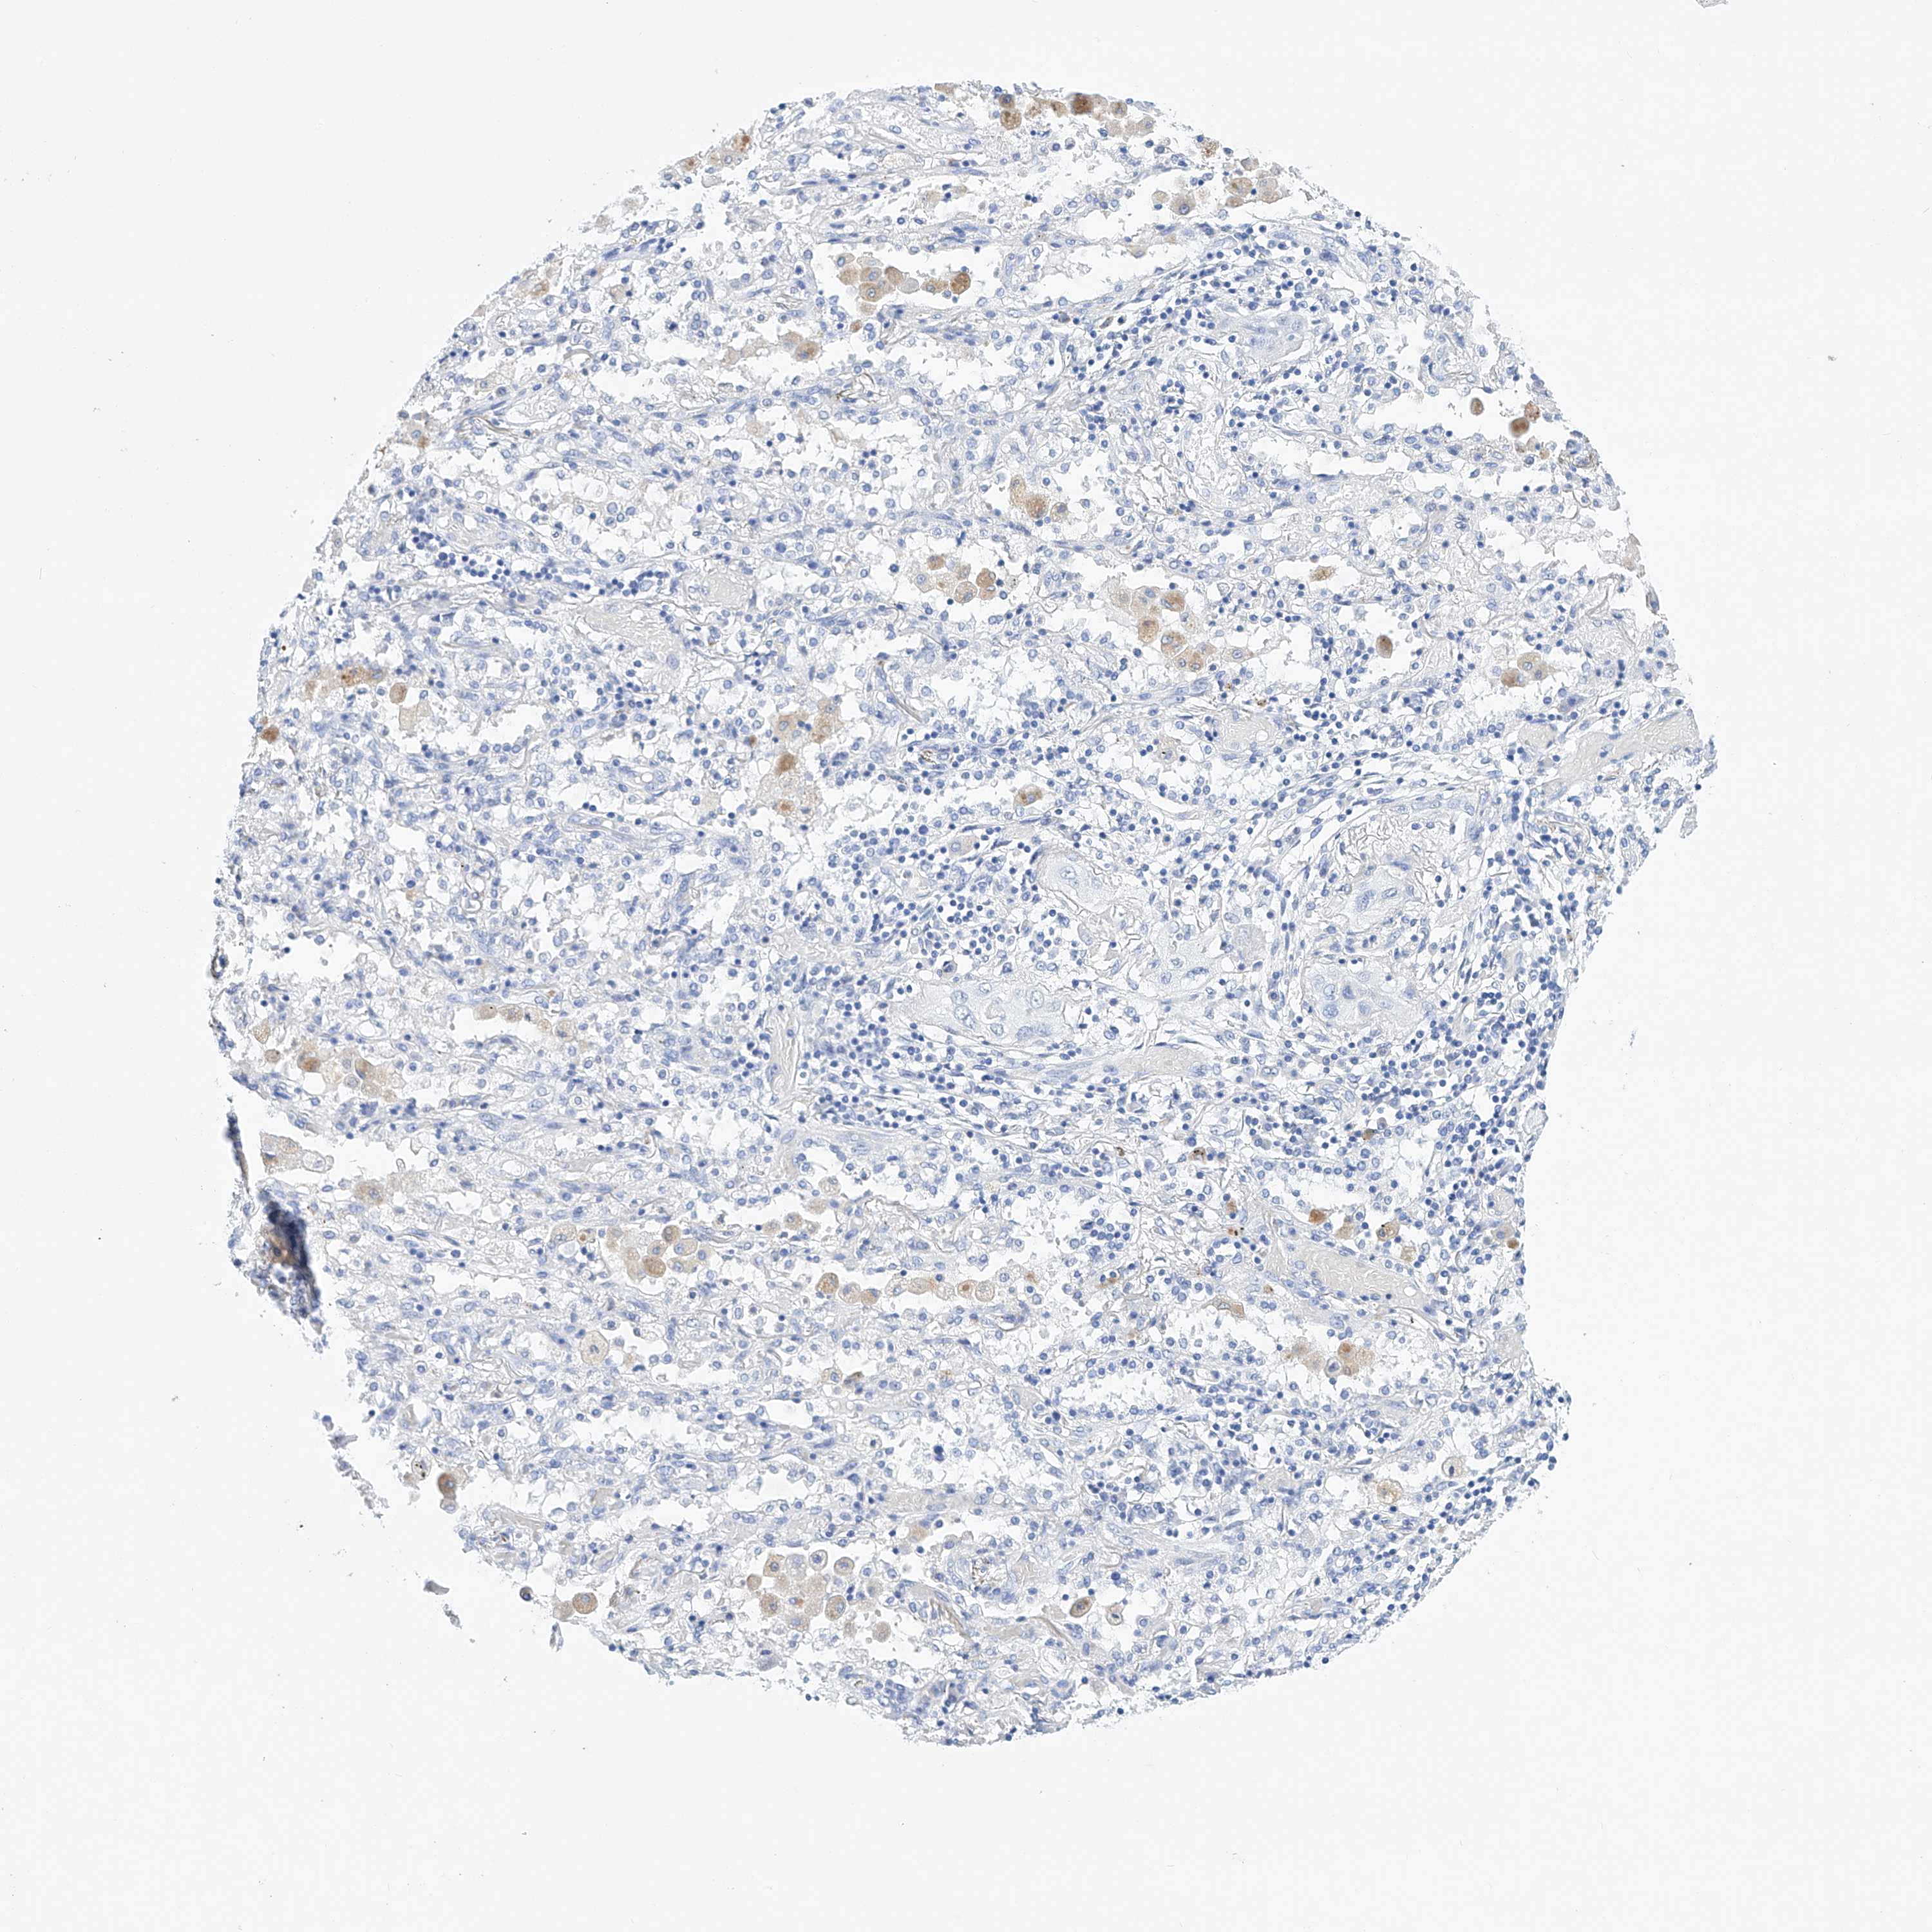

CANCER LUNG CANCER Show tissue menu

LUAD TCGA LUAD VALIDATION LUSC TCGA LUSC VALIDATION PROTEIN LUAD CPTAC PROTEIN LUSC CPTAC PROTEIN EXPRESSION

ANTIBODIES

AND

VALIDATION